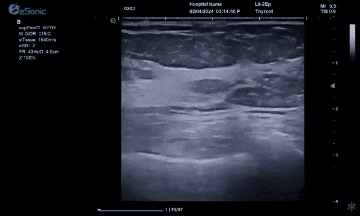

银河官网医疗(ESI)表示,其最新的人工智能功能可以帮助到医疗机构的工作效率,功能包括,实时、动态、快速自动识别病灶,良恶性病灶概率预测,甲状腺结节和乳腺的二维灰阶动态自动实时检测需求,提供多个结节动态检测轮廓框。实时获取多幅具备临床特征(大小、属性等)的结节切面,同时提供当前切面所示结节的结节大小、属性特征、TI-RADS 分级。

对于甲状腺结节相关的自动检测功能,甲状腺结节病灶检出率≥95%,良恶性分类灵敏度≥90%、良恶性分类特异度≥85%。